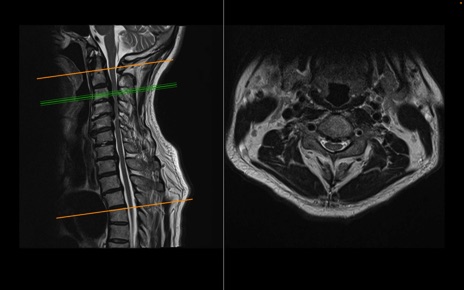

頚椎MRI

T2WI(横断像)

T2WI(矢状断像)